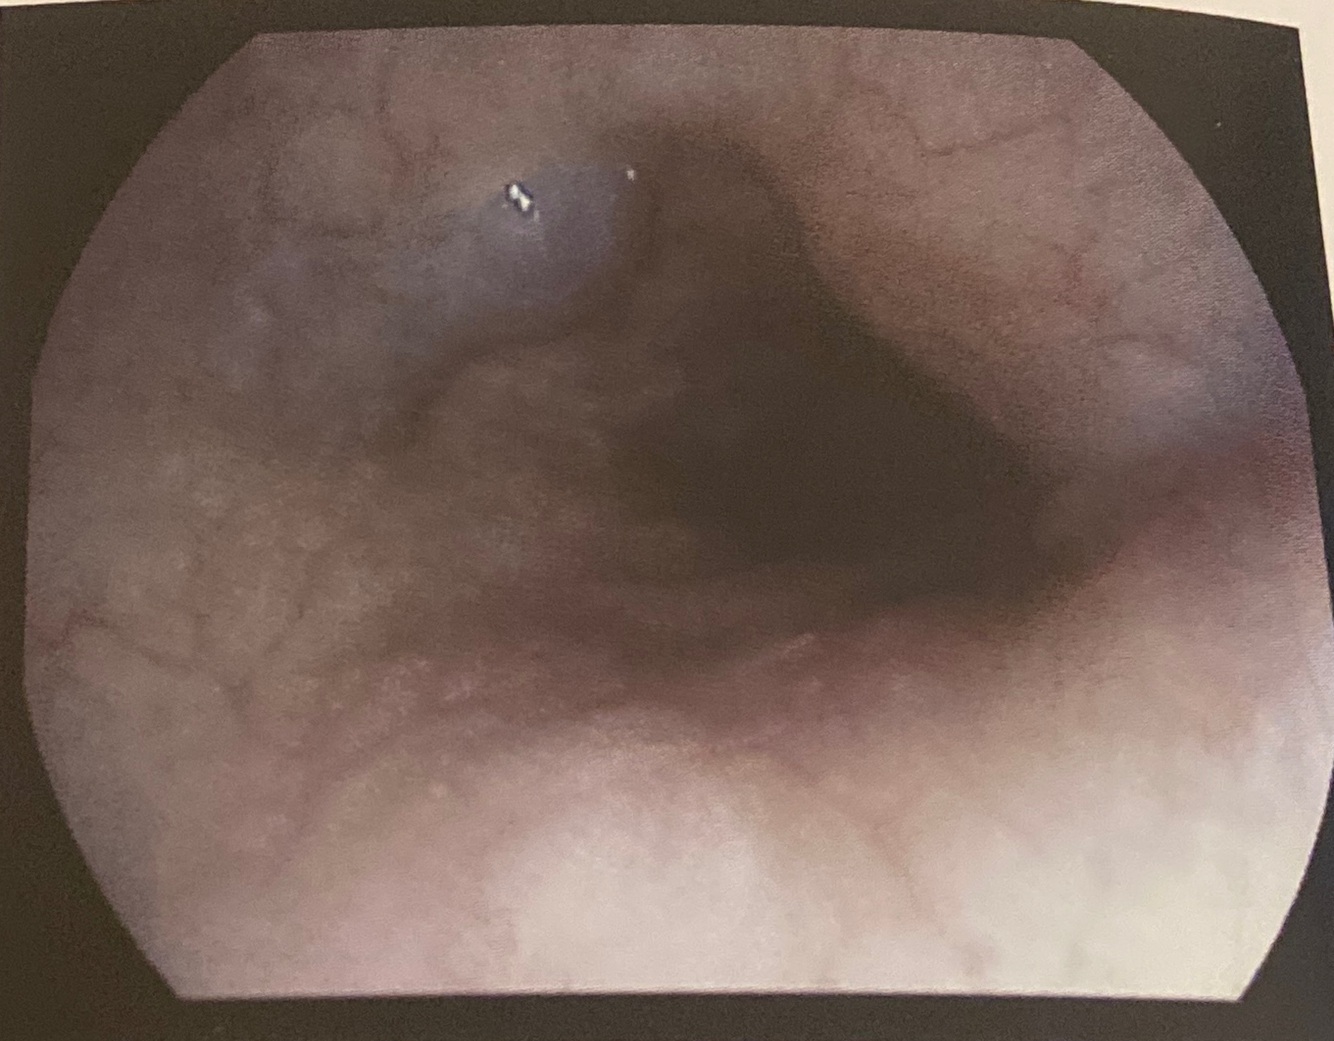

Aspectos endoscópicos do megaesôfago: dilatação, mucosa espessada de estase, estase alimentar